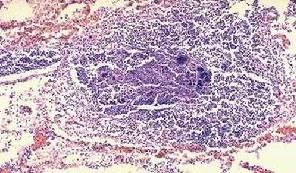

貓病毒性鼻氣管炎確診時需要進行特異性的血清學反應或病毒分離才能做出準確診斷。也可用病貓眼結膜和上呼吸道黏膜塗片或做組織切片,用FHV-1螢光抗體染色,可做出準確快速診斷。